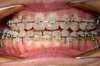

Intra Orale Droite

Intra Orale Face

Intra Orale Gauche